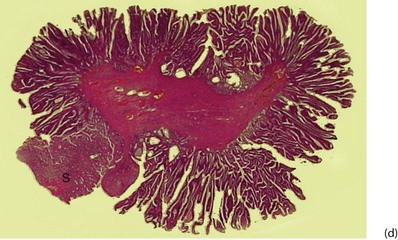

Fig. 27.1 Colorectal polyps

(a) This 65-year-old man was found to have positive faecal occult blood on colorectal cancer screening. This CT colography image shows a solitary polyp in the sigmoid colon, later removed by colonoscopic snaring. It proved to be a benign adenoma. (b) A 2 cm polyp on a long stalk in the sigmoid colon. (c) The snare loop is tightened around the stalk of the polyp before applying diathermy current to remove it and coagulate the blood vessels in the stalk. (d) Adenomatous polyp having mainly villous glandular architecture. The example shown has a well-defined stalk S, although this is more typical of tubular or tubulo-villous polyps, villous adenomas often having a broad base

Tubulo-villous adenomas are intermediate between tubular and villous adenomas and comprise the majority of colonic polyps (Fig. 27.1d). Most are pedunculated, and the stalk is covered with normal colonic epithelium. The stalk probably develops by peristalsis dragging the tumour mass distally and can range from about 0.5 to 10 cm long.